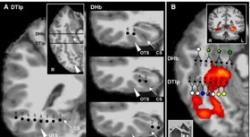

این توهمات، زمانی که «پیر مگه‌وند» از «موسسه فاینستاین» در نیویورک الکترودهایی را در درون مغز یک مرد جوان با هدف جستجوی منشا صرع وی کاشت، ظاهر شدند. این امر شامل حفاری روزنه‌های ریز در جمجمه وی‌ بود که از طریق آن، پزشکان دو الکترود پنج سانتی‌متری را وارد کرده و آن‌ها را به نقاط خاصی از بافت مغز هدایت کردند.

دکتر مگه‌وند نخست با استفاده از ام‌آر‌آی کاربردی و زمانی که بیمار به تصاویری از اشیا و صحنه‌های مختلف نگاه می‌کرد، از مغز وی اسکن گرفت. سپس فعالیت الکترودهای کاشت‌شده زمانی که وی به مجموعه‌ای مشابه از تصاویر نگاه می‌کرد، ضبط شد.

تیم علمی دریافت ناحیه‌ای از قشر مغزی در اطراف هیپوکامپ زمانی که سوژه به تصاویری از مکان‌ها نگاه می‌کرد، فعال می‌شد. این نقاط ریز بافت‌هایی بودند که به نظر می‌رسید به خانه‌ها و مکان‌ها بیش از دیگر اشیا اهمیت می‌دهند. الکترودهای کاشته‌شده برای تحریک مغز در این ناحیه به کار رفتند و مجموعه‌ای از توهمات بصری تولید شدند.

مرد جوان در ابتدا تماشای یک ایستگاه راه‌آهن آشنا و سپس بخشی از منزلش را گزارش کرد، اما هیچ بو یا صدایی با این صحنه‌ها مرتبط نبود. زمانی که تحریک این نواحی مغزی تکرار شد، همان توهمات اتفاق افتاد. هنگامی که محققان الکترودها را در بخشی اندکی متفاوت و در شکنج گیجگاهی تحتانی تحریک کردند، داوطلب عنوان کرد که چهره‌ها به ناگاه از ریخت افتادند.